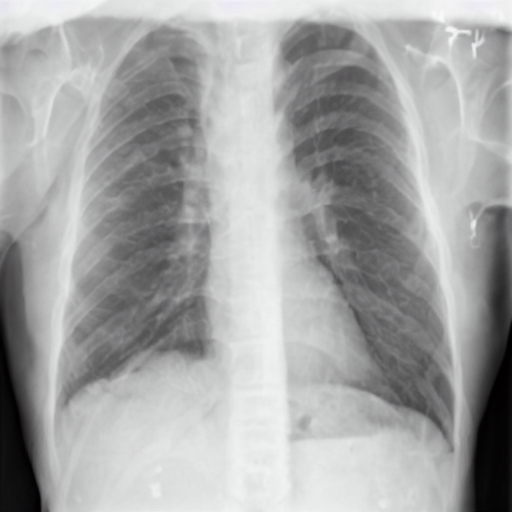

4.1 Qualitative Evaluation of Healthy Counterpart Generation

Example images from the disease COVID-19 Radiography Database and their generative healthy counterparts are given in figure 2. The images on the far left are instances of the lung opacity class from the real images in the dataset. The images in the middle column are examples of the generated healthy counterfactuals obtained via latent space diffusion, with RadBERT-guided textual-conditioning via a conditional prompt “normal chest x-ray”. A total of 75 diffusion inference steps are used with image conditioning strength=0.85 and guidance scale=7.5. (The former indicates the level of constraint on changes to the original input image and the latter is the weight given to the textual encoder conditioning in the generation of the image, ranging over [0,1] and [0,9], respectively).

Side-by-side inspection of the generated healthy counterfactuals (as per fig. 2) suggests that, as required, only minimal perturbation is made to the original image with respect to healthy pixels -i.e. localized image sites without structural medical defects. (In the top row, the medical structural defect in the original image is due to a lung opacity, and characterized via a relatively complex interaction between the imaging modality and subject manifesting as ‘gaps’ in the corresponding portions of the lung scan). The healthy/non-healthy discrepancy maps in all of these cases are obtained via masked subtraction of the original image from the generated image (the ground truth segmentation masks correspond to the broad area of interest –i.e. the complete lung). The generated healthy tissue is thus a subset of the mask and is shown in the final column of fig. 2 for the respective cases.

In the context of a VANT-GAN[20]-based approach, this highlighted material constitutes the diagnostic counterfactual visual attribution, i.e. the selection of material relevant to the diagnosis of the unhealthy condition. Healthy counterfactual generation was performed for the complete datasets in the three unhealthy classes, i.e Lung opacity, Viral Pneumonia and COVID, examples of which are given in fig. 3 for the three classes (all of the generated healthy counterfactuals from this experiment can be found on https://huggingface.co/ammaradeel/diffusionVA). Visual inspection indicates that the generated counterfactuals are, in general, visually plausible with minimal perturbation made to the unhealthy image overall. Moreover, the healthy counterpart generation does not appear to unnecessarily affect aspects of the images unrelated to the medical condition, the model selectively making changes to the unhealthy regions in a structurally plausible manner, e.g. generating missing portions of the lung without generating extraneous lung material where it would be expected to normally exist (e.g. in the abdominal cavity).